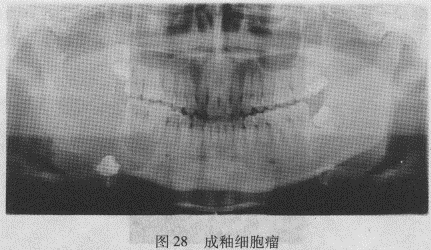

5.成釉细胞瘤X线上成釉细胞瘤表现多样化,可分为4型:

(1)多房型:占80%~90%,特点:分房大小相差悬殊、成群排列、相互重叠,各房一般圆形或卵圆形,房间隔可以是锐利光滑高密度骨嵴,也可以是密度略淡的纤维间隔,病变边界清楚。

(2)蜂窝型:较少见,其特点大小基本相等的小分房,房隔厚且粗糙不均匀,多为真性骨嵴,边缘清晰。完全呈蜂窝状改变的成釉细胞瘤并不多见,其多与成釉细胞瘤的多房型或单房型的大房同时存在。

(3)单房型:单房状低密度影像,边缘呈分叶状,有切迹,或出现双边影像。

(4)局部恶性征型:该型成釉细胞瘤最少见,X线片上显示受侵的颌骨无膨隆改变,颌骨骨小梁和密质骨溶解消失,边界不清,呈虫蚀样改变,此表现颇似颌骨恶性肿瘤,但成釉细胞瘤瘤内边缘残留的不全房隔可与恶性肿瘤鉴别。这种肿瘤在临床上生长较快,有反复出血史。

成釉细胞瘤的X线表现除上述4型外,还有一些共同的X线特征:①单房或多房低密度影像区(骨质破坏区);②界限清楚,形态欠规则,颌骨膨隆以唇颊侧为主;③肿瘤内可含牙或不含牙;④受累的牙齿牙根呈截断状或锯齿状吸收;⑤肿瘤区内的牙齿可被推移位或脱落;⑥肿瘤周围可有骨硬化现象(图28)。

成釉细胞瘤的X线表现除上述4型外,还有一些共同的X线特征:①单房或多房低密度影像区(骨质破坏区);②界限清楚,形态欠规则,颌骨膨隆以唇颊侧为主;③肿瘤内可含牙或不含牙;④受累的牙齿牙根呈截断状或锯齿状吸收;⑤肿瘤区内的牙齿可被推移位或脱落;⑥肿瘤周围可有骨硬化现象。